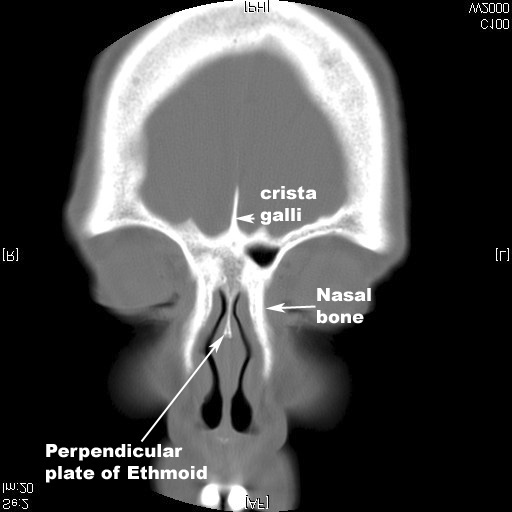

Its upper part rises above the cribriform plate as the crista galli. Three views of the ethmoid bone by Anatomy Next Ethmoidal labyrinth. The ethmoidal labyrinth is a paired structure of the ethmoid bone situated in the sagittal plane below the lateral margin of the cribriform plate.

Paranasal Sinuses. Paranasal sinuses refer to a group of air-filled spaces around the nasal cavity (a system of air channels that connect the nose with the back of the throat) (1). They facilitate the circulation of the air breathed in and out of the respiratory system (2). Paranasal sinuses have four different pairs: maxillary sinuses, frontal ... My house has no rooms that are all interior walls. My house is wood with a crawl space. I live in Northern Alabama. Is there any preferred room to stay in that would be best? My closets have hanging doors and wouldn't do a thing to protect. House built in 77. ​ [https://i.imgur.com/TLhRkGa.png](https://i.imgur.com/TLhRkGa.png) ​ Any suggestions? Download scientific diagram | Aeration of the crista galli. from publication: CBCT Imaging of Paranasal Sinuses and Variations | Paranasal sinuses located in the bones surrounding the nasal cavity ... crista galli - prominent ridge in the middle of the cribriform plate and an attachment point for the falx cerebri. lateral masses - entire bony masses attached on either side of the cribriform plate. The lateral masses include: superior nasal conchae and middle ...

The crista galli is a midline upward projection to which the falx cerebri attaches. On either side of the crista galli, the cribriform plate has grooves that hold an olfactory bulb. Tiny foramina in the cribriform plate allow for the transmission of the olfactory nerves.

Download scientific diagram | Coronal CT scan of the human skull showing a large cavity within the crista galli. Maximall width and hight could be measured in this projection. This type of ...

The crista galli is a sail-like projection located at the top/superior portion of the ethmoid bone. The crista galli is where the membrane around the brain attaches, thereby preventing the brain from moving around in the skull. It essentially serves as an anchor point for the brain.